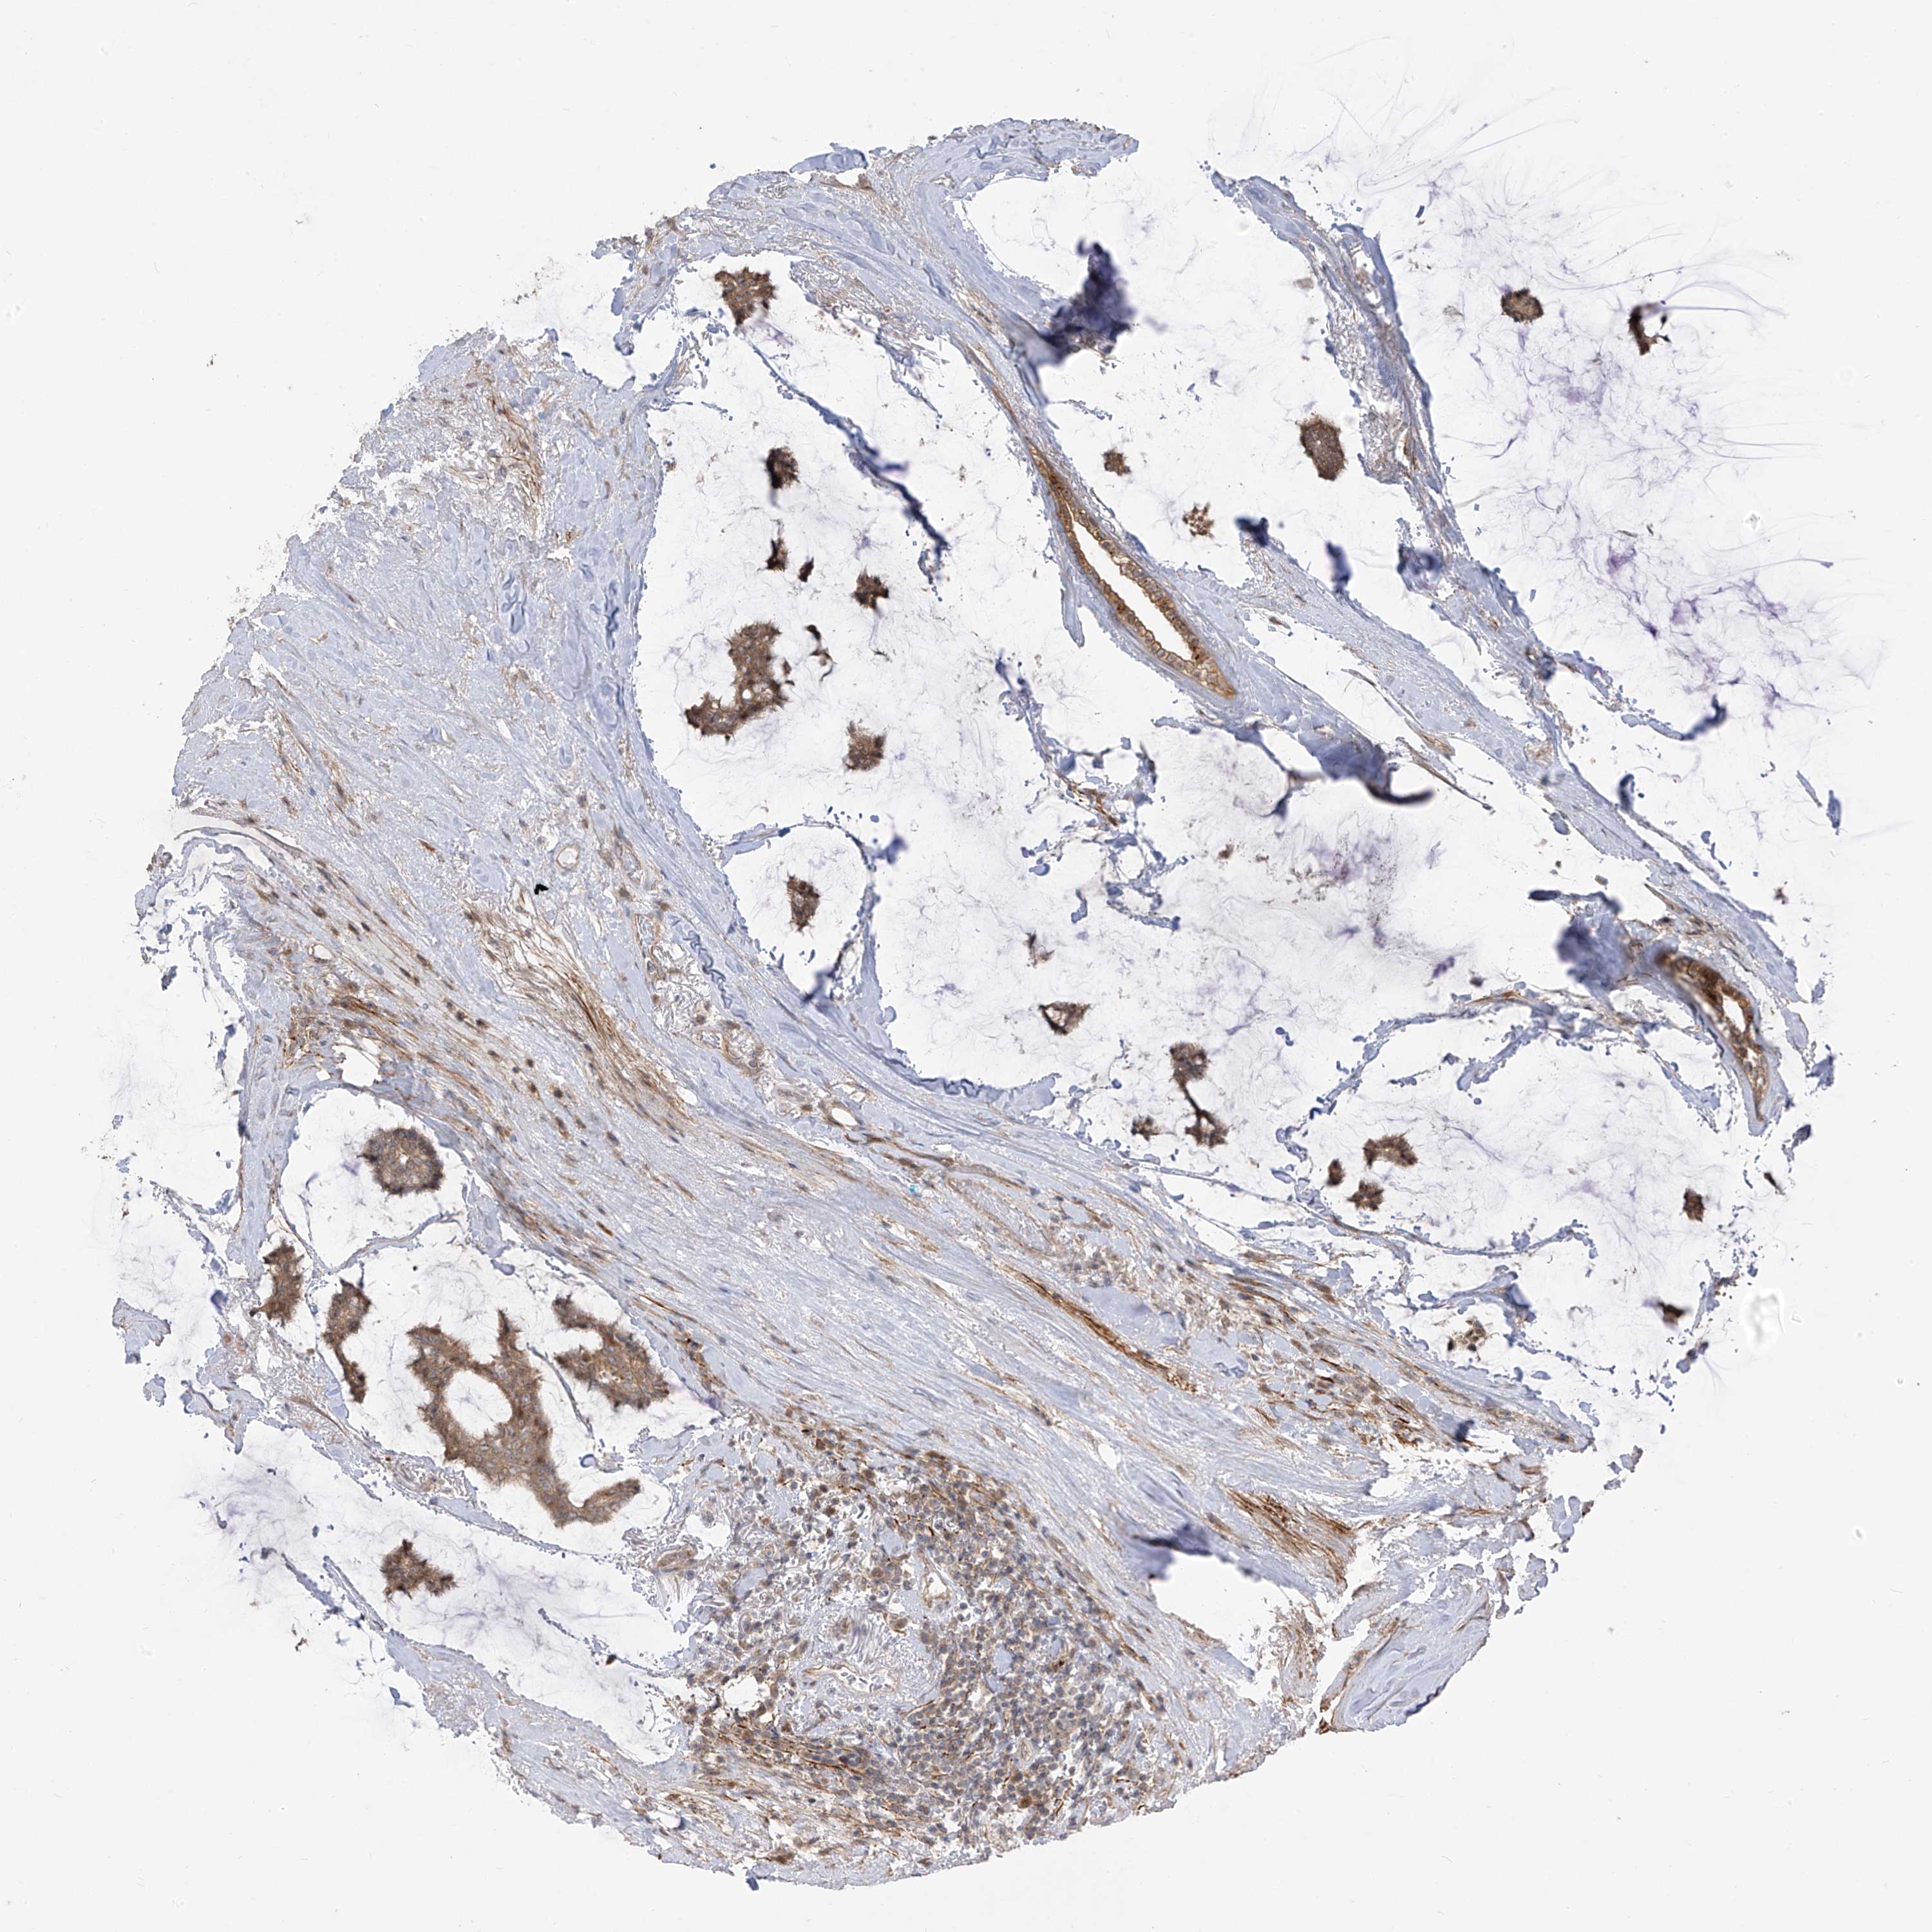

CANCER BREAST CANCER Show tissue menu

BRCA TCGA BRCA VALIDATION PROTEIN EXPRESSION

ANTIBODIES

AND

VALIDATION